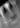

Вот так на рентгенограмме выглядит периодонтит. На снимке явно виден не до конца запломбированный корневой канал, который и спровоцировал заболевание. Так же на снимке визуализируется довольно обширный воспалительный процесс за верхушкой корня, отмеченный стрелкой.